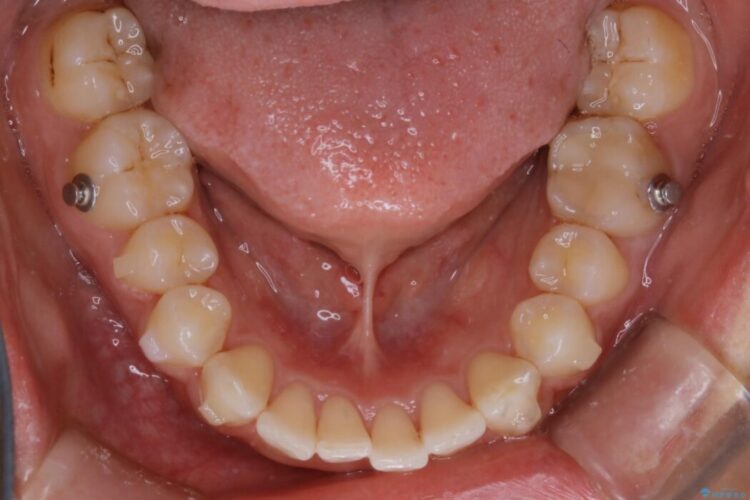

下の歯列よりも上の歯列が前に出ている状態を治すため、マウスピース矯正に加え、患者様にゴムかけのご協力をいただきました。その結果、ガタつきが改善し、上下の噛み合わせが適切な位置で合うようになりました。

歯列弓の拡大

歯並びが悪くなる原因の一つに「歯列弓の狭窄」というものがあります。

奥歯や前歯が内側(舌側)に倒れ込んでしまったり、歯が生えてくる位置が内側になってしまうことにより歯並びのアーチが狭くなってしまうことを言います。

このような場合、歯並びのアーチを拡大してあげるだけでもガタつきを無くすためのスペースがかなり作れることがあります。